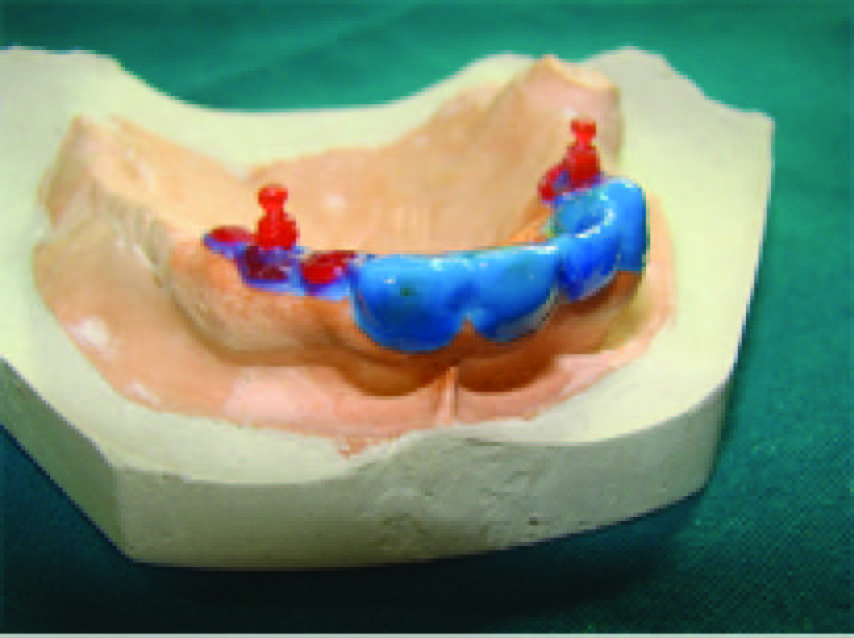

The treatment planning for prosthetic rehabilitation for this patient was made after considering the age of the patient, multiple missing teeth and long standing partial edentulism. For the purpose of improved aesthetics and elevated psychological acceptance of the prosthesis by the patient, precision attachment retained interim removable partial denture was planned in the maxillary arch [5]. Due to poor periodontal condition of lower anterior teeth, a conventional clasp retained interim removable partial denture was planned for the mandibular arch [6]. The enlarged pulp chambers of the anterior teeth carried a risk of perforation during tooth preparation and hence 21, 11, 13 were root canal treated. Primary impressions of the upper and lower arch were made. Casts were prepared with type III dental stone. Temporary baseplates and wax occlusal rims were fabricated and a tentative jaw relation was carried out to confirm that adequate inter-arch space was available for fabrication of precision attachment retained prosthesis. Tooth preparation for porcelain fused to metal bridge was done on 21, 11, and 13 [Table/Fig-5]. Anatomic impression of the upper arch was made in putty elastomeric impression material and light body. Anatomic cast was prepared in type 4 dental stone. Porcelain fused to metal bridge was fabricated on this anatomic cast on the prepared abutments of 11, 13 and 21 [Table/Fig-6]. The extra coronal precision attachment that is the O-ring posts (male patrix) were incorporated distal to 13 and 21 in the porcelain fused to metal bridge [Table/Fig-7]. Following trial, finishing and polishing, this porcelain fused to metal bridge with the extracoronal precision attachments was cemented permanently in the patient`s mouth with Glass inomer cement on the abutment teeth 11, 13 and 21 [Table/Fig-8]. Functional impressions of the upper and lower arch were made and master cast was poured in dental stone type IV [7]. Jaw relation, try in and fabrication of the removable partial dentures in the upper and lower arches were then carried out sequentially. The female matrix namely the O-rings were incorporated into the upper partial denture in correspondence to the male patrix that is the O-ring posts [Table/Fig-9]. The removable partial dentures were inserted in the patient’s mouth after minor adjustments in the occlusion [Table/Fig-10,11]. The patient was educated about the usage and maintenance of the prosthesis. Follow-up appointment was scheduled after 3 months to study bone growth and plan for a definitive prosthesis.

O-ring incorporated upper partial denture and lower conventional removable partial denture,